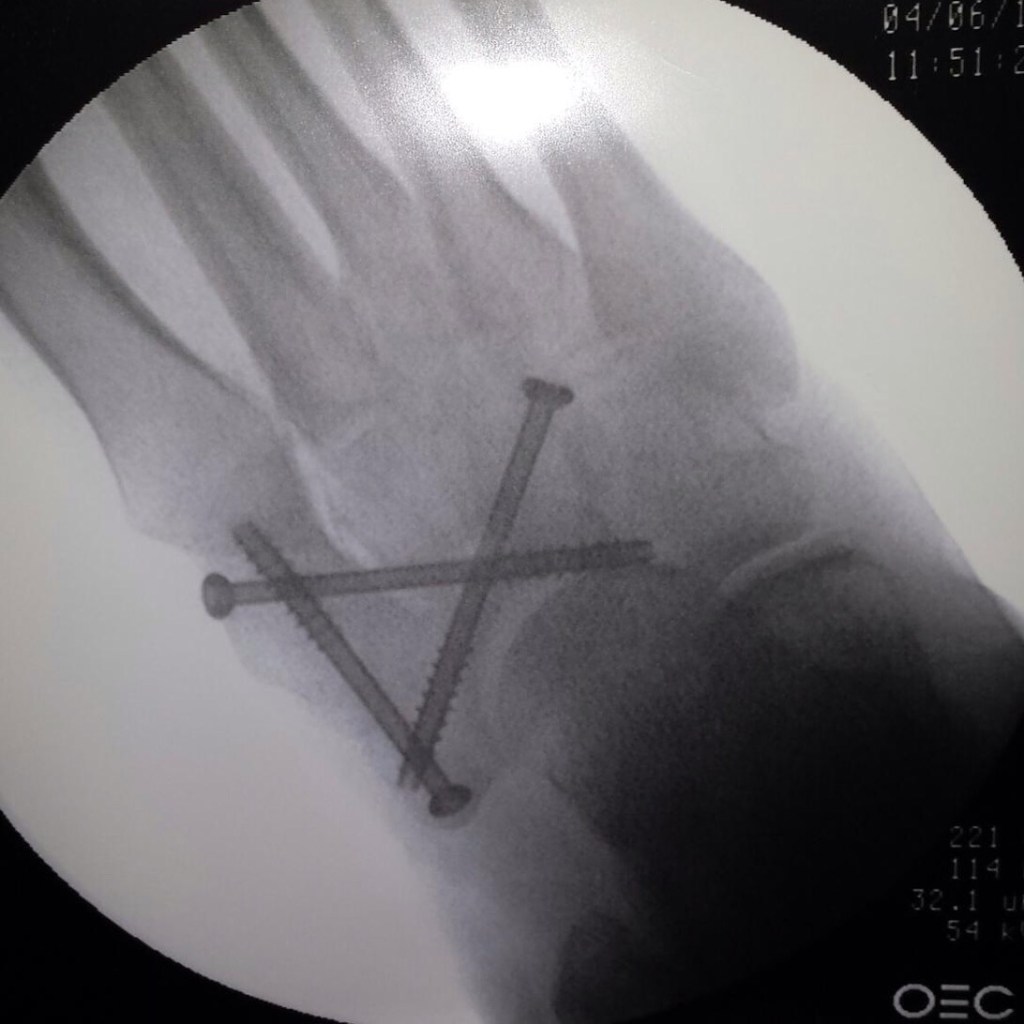

The feelings I share come from the frustration, anger, and discouragement that followed my pain management appointment last week. I was seen by an NP and shared about how I’m living in the upper half of the pain scale on a regular basis with no relief. I even shared my consideration of amputation. That’s how bad the pain is most of the time and I feel that should speak loud and clear about where I am in this journey.

What I left with was a recommendation to use topical treatments, do yoga, and an Rx for a strong, once daily dose, of what I understand is Ibuprofen. There was even mention of seeking an Rx for marijuana. Ummm, NO!!! Be it the truth or not, what I walked away with is, “Ok, we sold you the implant, it’s in, we’ve got our money, sorry you’re still in pain but there’s nothing else we can do for you.”

I have another follow up appointment with my doctor in early December. I’ll see what his response is and that will help me determine the next best step. Regardless, I feel compelled to move forward with a second and even third opinion in regards to my foot and my pain. So now what? That’s a rhetorical question.